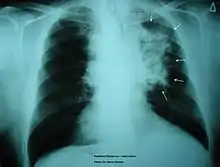

The morbidity of cigarette smoking is nearly 50% with 7 million first-hand smokers and 1.2 millions second hand smokers killed each year.[8] Regardless of active or passive smokers, macrophage accumulation is found in the lungs.[3][5] The diagnostic methods for smoke-related diseases include bronchoalveolar lavage which can also be used for examining smoker's macrophages in addition to augmented inflammatory cells in the alveolar lumen.[1]

The immune functions in smoker’s macrophages are compromised, so the airway pathogens are more likely to accumulate and cause infection.[17] Smoker’s macrophages have reduced expression of HLA-DR antigens, causing immunosuppression.[18][19] In addition, nicotine impairs the phagocytosis of M. tuberculosis and also induces immunosuppression via the activation of alpha-7 nicotinic receptors.[4][17] Meanwhile, due to the impaired TLR2 and TLR4 signaling, macrophages fail to recognize pathogens, so there is a decrease in pathogen clearance.[17] Therefore, smokers are prone to acute respiratory tract infection and community acquired pneumonia.[20]

Chronic Obstructive Pulmonary Disease